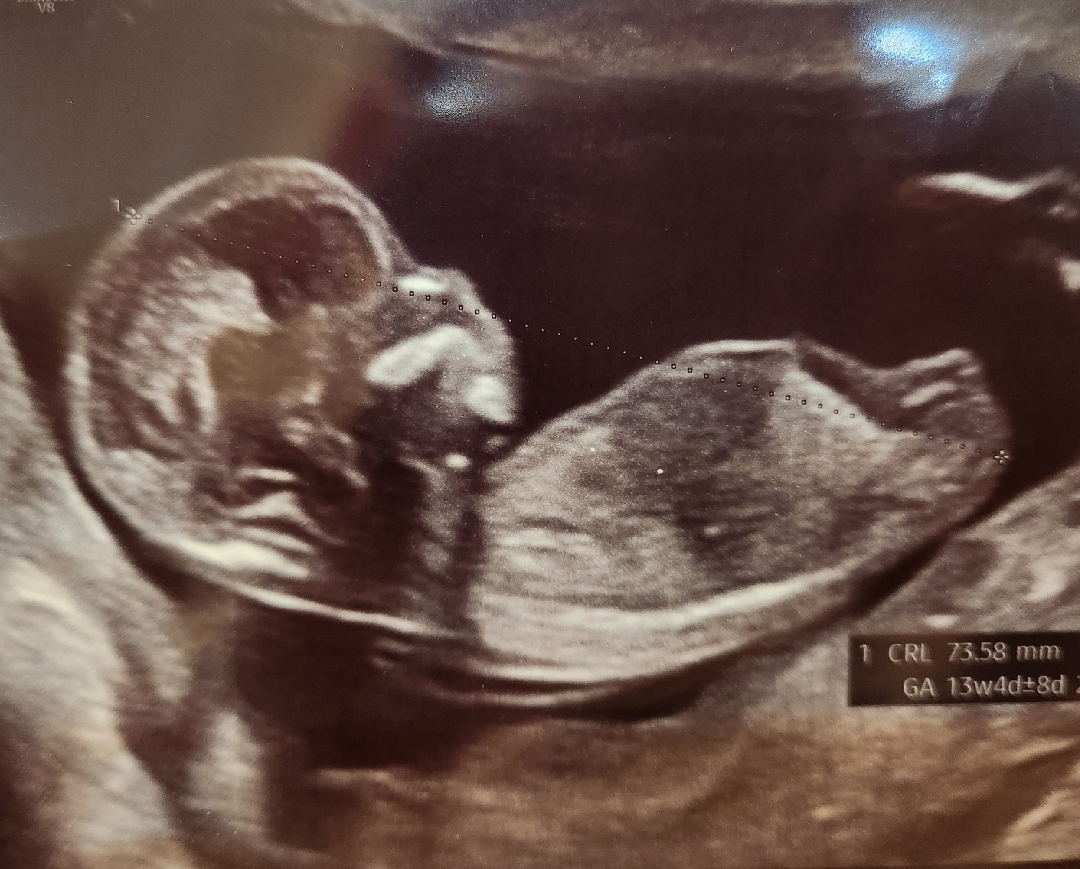

첫째딸인데 둘째도 딸일까요..?

딸 같아 보이긴 한데.. 어때보이시나요?ㅎㅎ